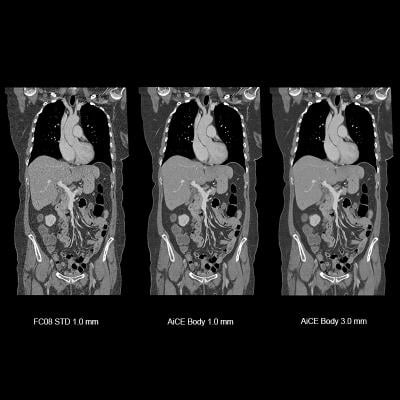

Image courtesy of Canon Medical Systems

October 21, 2019 — Canon Medical Systems USA Inc. has received U.S. Food and Drug Administration (FDA) 510(k) clearance on its Advanced Intelligent Clear-IQ Engine (AiCE) for the Aquilion Precision computed tomography (CT) system. The clearance further expands access to Canon’s new deep convolutional neural network (DCNN) image reconstruction technology. This technology, now available on both the Aquilion Precision and Aquilion One/Genesis Edition premium CT systems, uses a deep learning algorithm to differentiate signal from noise so that it can suppress noise while enhancing signal, forging a new frontier for CT image reconstruction.

Aquilion Precision, which Canon calls the world’s first ultra-high resolution CT, provides two times the resolution of conventional CT, revealing detail that is typically only seen in cardiac catheterization labs. With AiCE, the system now enables clinicians to perform super-high resolution studies at doses equivalent to standard resolution CT (with traditional hybrid iterative reconstruction techniques). AiCE learns from the high image quality of model-based iterative reconstruction (MBIR) to reconstruct CT images with improved high contrast spatial resolution.